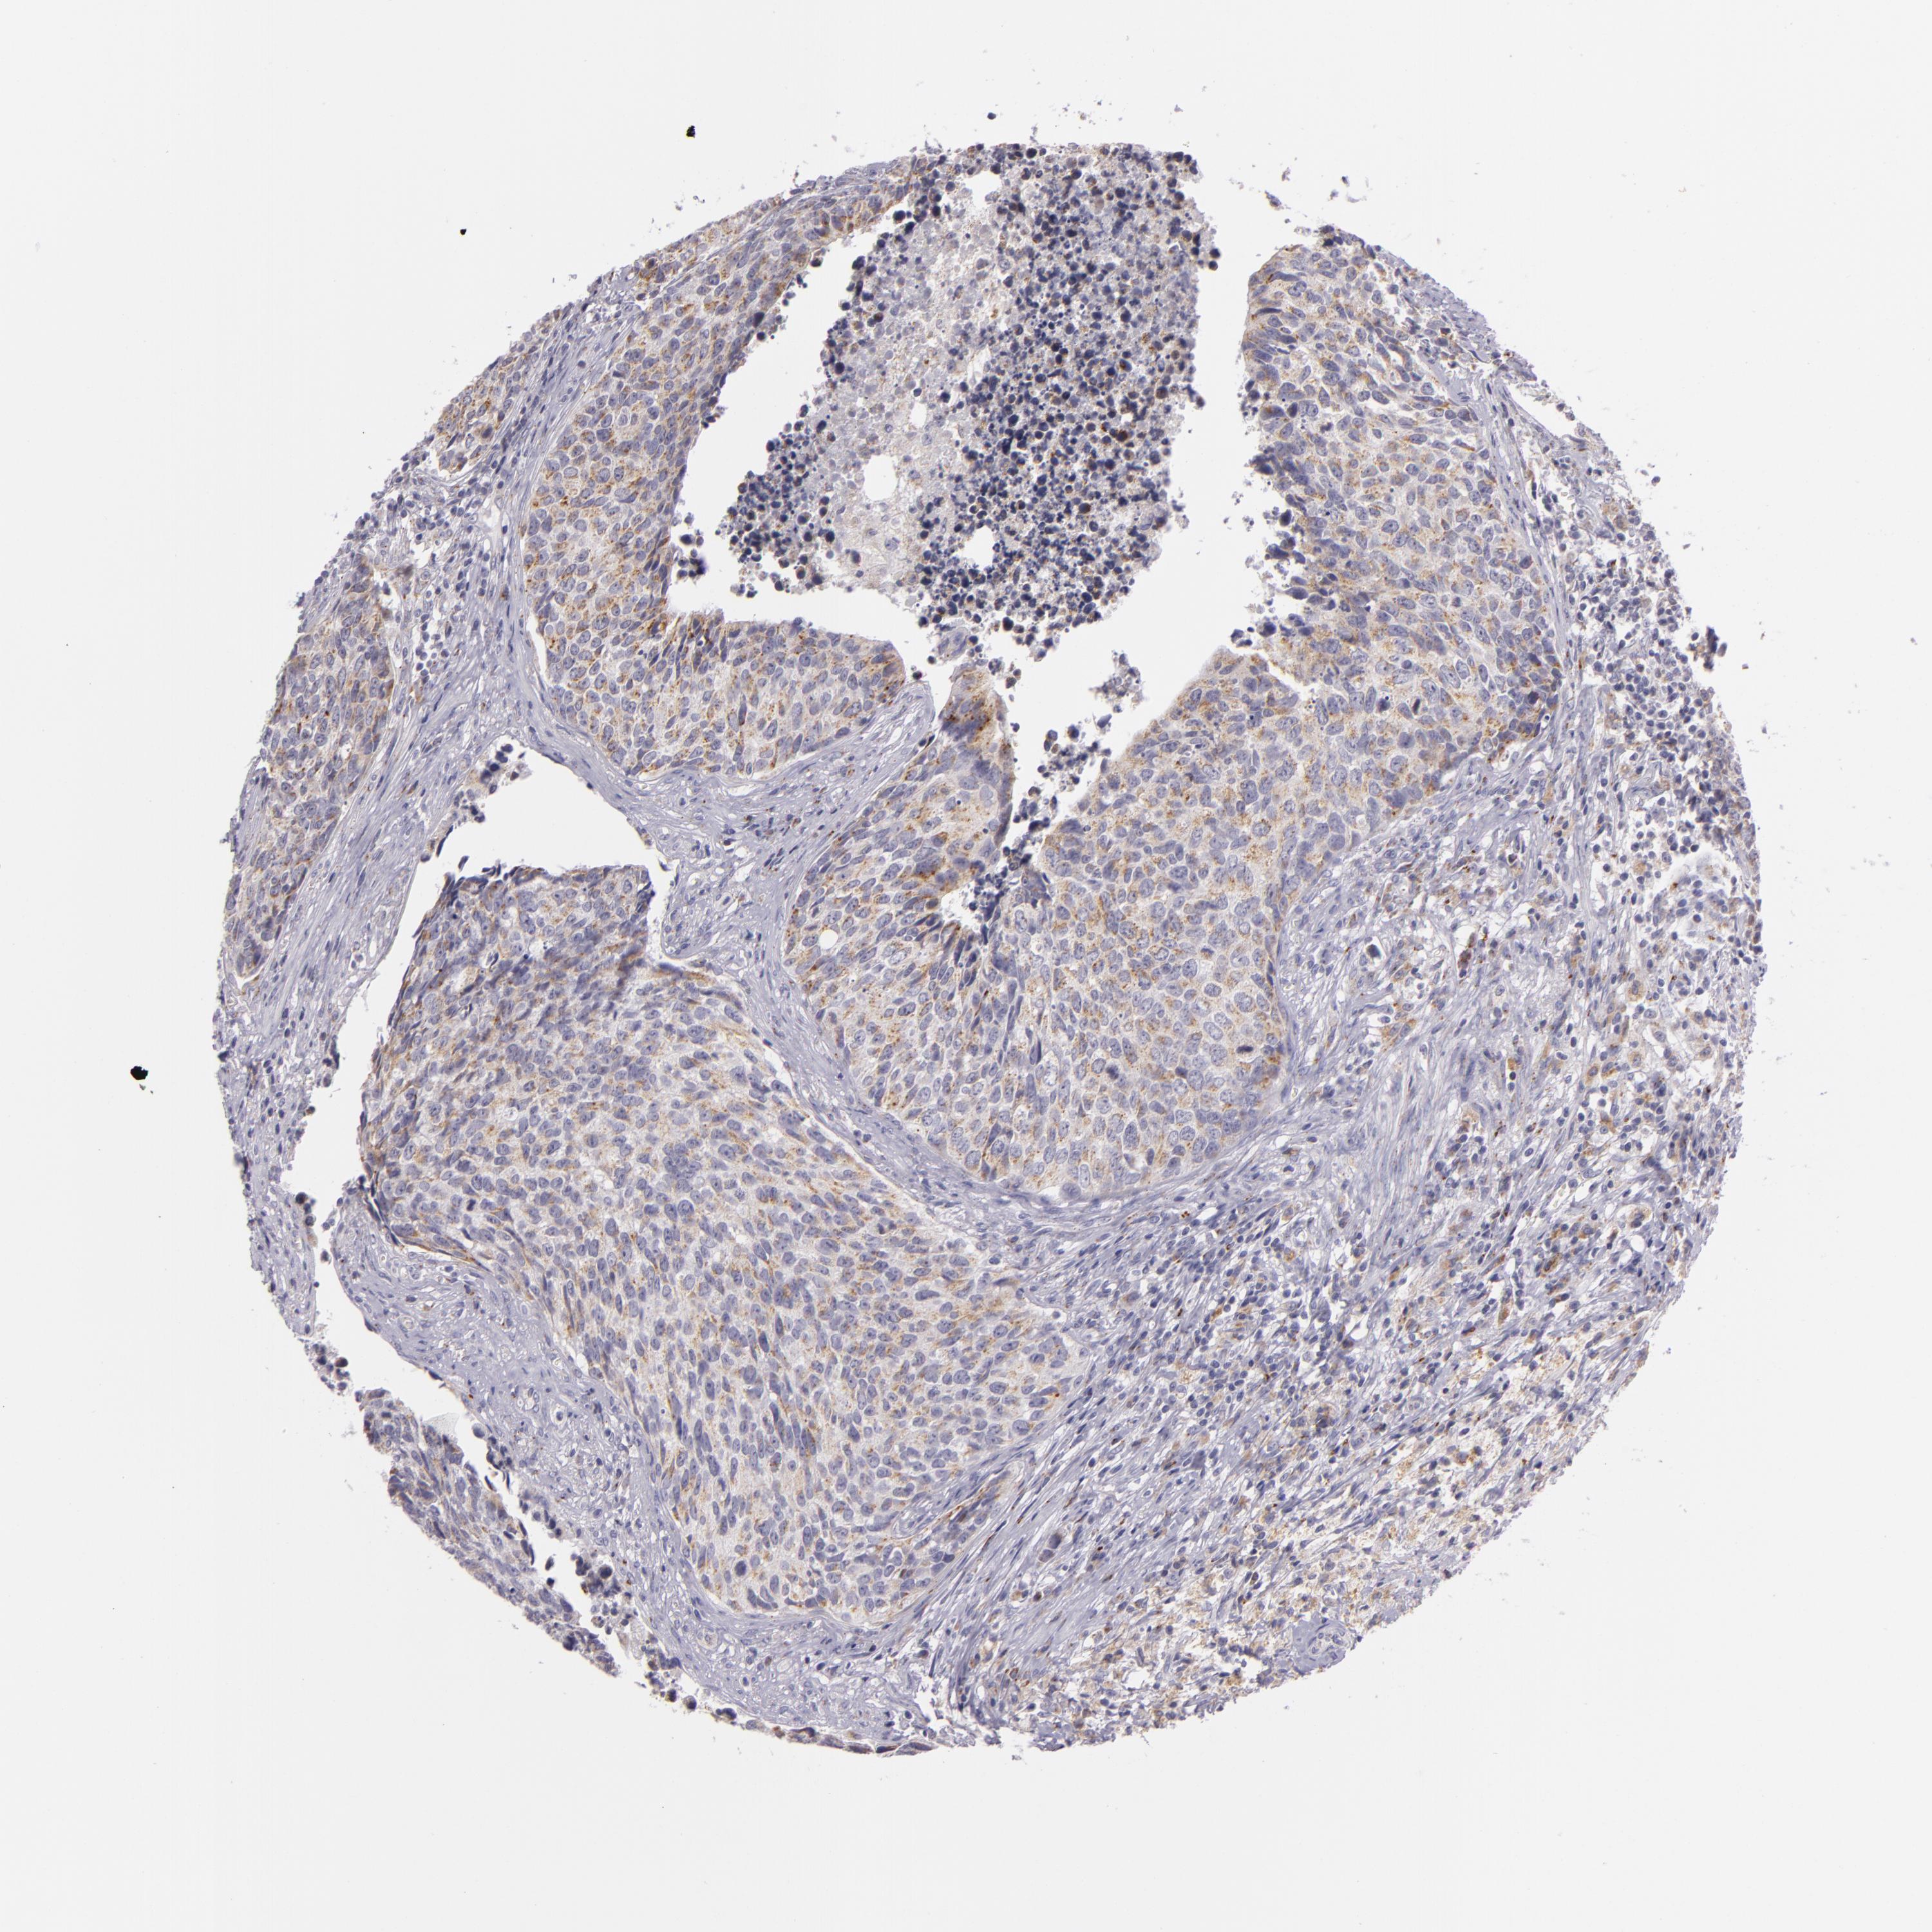

UROTHELIAL CANCER - Protein expressioni

A mouse-over function shows sample information and annotation data. Click on an image to view it in a full screen mode. Samples can be filtered based on level of antibody staining by selecting one or several of the following categories: high, medium, low and not detected. The assay and annotation is described here.

Note that samples used for immunohistochemistry by the Human Protein Atlas do not correspond to samples in the TCGA dataset.

Antibody stainingi

Antibody staining in the annotated cell types in the current human tissue is reported as not detected, low, medium, or high, based on conventional immunohistochemistry profiling in selected tissues. This score is based on the combination of the staining intensity and fraction of stained cells.

Each image is clickable and will lead to virtual microscopy that enables deeper exploration of all samples and also displays staining intensity scores, fraction scores and subcellular localization as well as patient and tissue information for each sample.

Antibody HPA001113

Staining

High

Medium

Low

Not detected

Intensity

Strong

Moderate

Weak

Negative

Quantity

>75%

75%-25%

<25%

None

Location

Nuclear

Cytoplasmic/membranous

Cytoplasmic/membranous,nuclear

Urothelial carcinoma, High grade

Urothelial carcinoma, Low grade

Adenocarcinoma, NOS